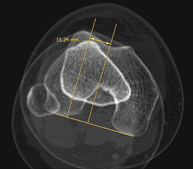

Exploració radiològica que mitjançant un sistema de raigs X i detectors que giren al voltant del pacient i que reconstrueixen les imatges per ordinador (TC Multidetector), permet l'estudi detallat dels ossos, els músculs i les articulacions del genoll. - TC de turmell-peu

Exploració radiològica que mitjançant un sistema de raigs X i detectors que giren al voltant del pacient i que reconstrueixen les imatges per ordinador (TC Multidetector), permet calcular una sèrie de mesures a nivell de maluc, genolls i turmells per solucionar problemes de rotació i angulació de les extremitats inferiors. - TC d'ossos llargs